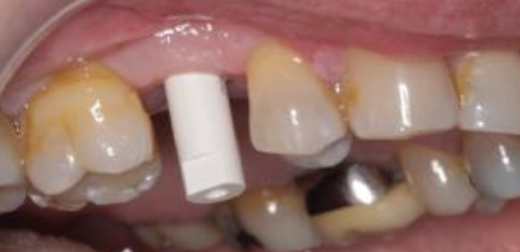

What is this?

Plastic snap-on device